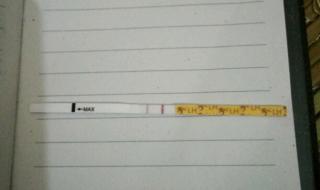

四、像怀孕了应该怎么准备

如果比较类似是怀孕了,应该及时到医院做hcg检查来确诊的,建议不要有压力,在确诊是怀孕后应该积极到医院建档预约产检,也不要有大的压力,算一下预产期的时间,看看身体的变化,观察早孕反应是否正常,平时应该做到营养均衡,不要劳累。